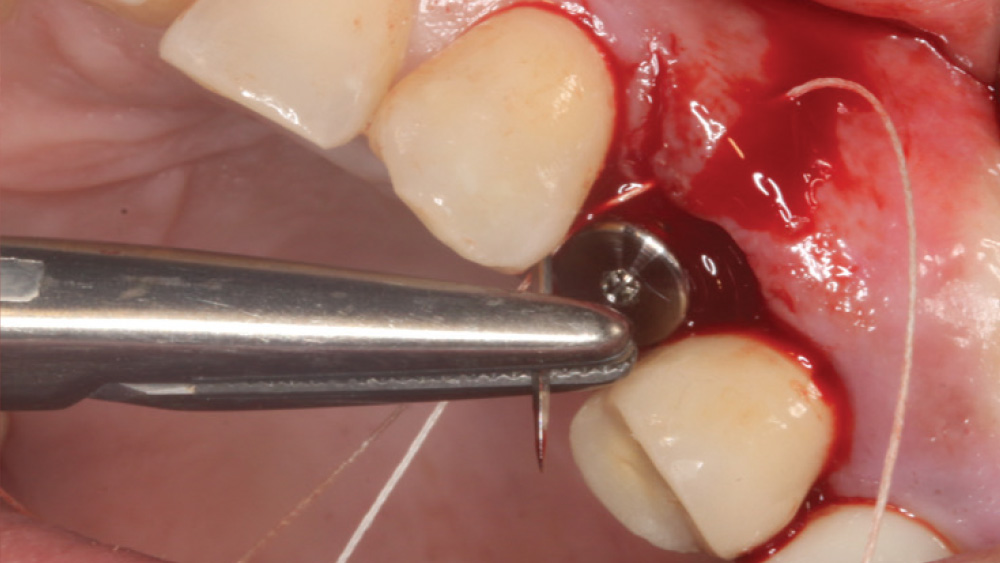

CASE REPORT

The following case, which I performed alongside Dr. Stephanie Tilley of Pensacola, Florida, illustrates the use of both surgical techniques for the same patient, who presented with edentulous spaces in the areas of both right and left maxillary first bicuspids. Due to varying soft-tissue volume on each side of the arch, implant surgery was performed using a flapless procedure for one site, while the attached gingiva was reflected to expose the available hard tissue for the other. As a result of proper site evaluation, treatment planning and restorative-driven implant placement, both surgical techniques led to successful outcomes for the patient.